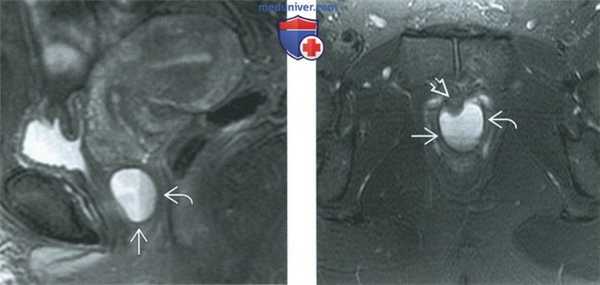

(Слева) При МРТ на Т2-ВИ FS в сагиттальной плоскости в передней стенке влагалища определяется крупная киста гартнерова канала. Визуализируются уровни жидкости, возникшие в результате имевшего место воспалительного процесса или кровоизлияния.

(Справа) При МРТ на Т2-ВИ FS в аксиальной плоскости у той же пациентки определяется киста гартнерова канала со слаборазличимым уровнем жидкости. У пациентки отмечались мочевые симптомы, обусловленные масс-эффектом, оказываемым кистой на расположенную рядом уретру.